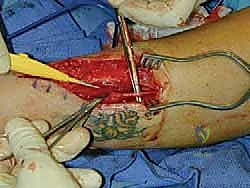

علاج قدم شاركو المعقدة: تقنية التصحيح التدريجي بالحد الأدنى من التدخل الجراحي ودمج المفاصل

اكتشف علاج قدم شاركو بتقنية التصحيح التدريجي ودمج المفاصل بالحد الأدنى من التدخل الجراحي على يد الأستاذ الدكتور محمد هطيف، الخبير الأول في …